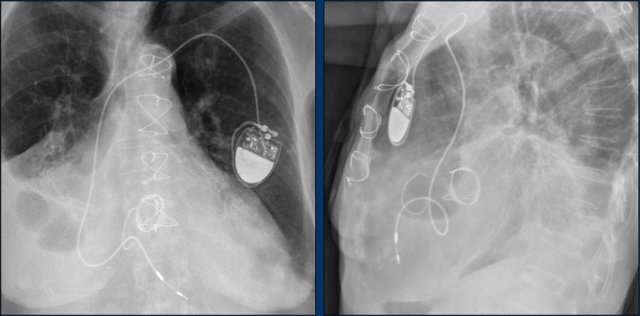

The findings are:

• Two epicardial leads connected to pacemaker

• ICD

• two leads to right ventricular apex

• one lead contains two shock coils

• tricuspid valve (arrows)

• mitral valve